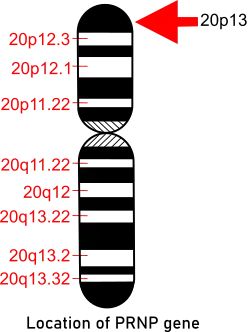

Fatal familial insomnia is a rare hereditary prion disease that is associated with the D178N-129M PRNP gene that is caused by a mutation. The gene PRNP that provides instructions for making the prion protein PrPC is located on the short (p) arm of chromosome 20 at position p13.[11] Both people with FFI and those with familial Creutzfeldt–Jakob disease (fCJD) carry a mutation at codon 178 of the prion protein gene. FFI is also invariably linked to the presence of the methionine codon at position 129 of the mutant allele, whereas fCJD is linked to the presence of the valine codon at that position. The disease occurs when there is a change of amino acid at position 178 when an asparagine (N) is found instead of the normal aspartic acid (D). This has to be accompanied with a methionine at position 129.[12]

FFI is an autosomal dominant disease that harbors a missense GAC to AAC mutation at codon 178 of the PRNP prion protein gene located on chromosome 20, along with the presence of the methionine polymorphism at position 129 of the mutant allele. Pathologically, FFI is characterized by predominant thalamic degeneration especially in the medio-dorsal and anterio-ventral nuclei. Phenotypic variability is a perplexing feature of FFI.